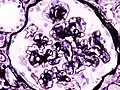

![]() Микрофотография узелкового гломерулосклероза при синдроме Киммельстил-Уилсона. | |

Гистопатологическая картина диабетического гломерулосклероза с нефротическим синдромом.

Синдром Киммельстил-Уилсона (диабетический гломерулосклероз) — узелковая форма гломерулосклероза, специфическая для сахарного диабета, получила название в честь патологоанатомов Киммельстил и Уилсона, обнаруживших и описавших в 1936 году своеобразное узелковое склеротическое поражение клубочков почек у лиц с сахарным диабетом. При диабете наблюдаются диффузный и узелковый варианты поражения почечных клубочков. Узелковая форма, описанная Киммельстил и Уилсоном, чаще встречается при сахарном диабете 1-го типа уже вскоре после манифестации заболевания, постепенно прогрессирует, приводя в итоге к диабетическому гломерулосклерозу и развитию ХПН. В клинической практике термином «синдром Киммелльстил-Уилсона» характеризуют нефросклеротическую, азотемическую стадию поражения почек при сахарном диабете. Последнее время этим термином пользуются реже, пользуясь диагнозом «Диабетическая нефропатия, хроническая болезнь почек 5 стадии» (Ефимов А. С. и соавт.)[3].